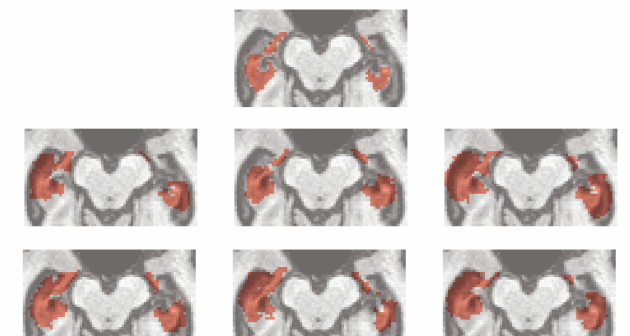

4.1 Segmenting the Hippocampus of a Single Diseased Brain

We take as our target the three-dimensional brain image of a 78 year old male diagnosed with AD. The six controls are registered to the target brain. To reduce the size for the sake of computation without losing information about the plausible location and volume of the hippocampus of interest, the images are cut to three-dimensional rectangles of the same size, where the rectangle is the smallest box containing the largest segmentation. This results in each image having dimension so that and in (1). One representative slice from each of the resulting three-dimensional atlas segmentations is displayed in Figure 7, along with the same slice from each of the manual segmentations. In this figure we observe a systematic tendency for each atlas to considerably over-segment the hippocampus when compared to the manual segmentation. This is due in part to the fact that each atlas is based on a brain that has not been diagnosed with AD. It is well established that hippocampal atrophy is more severe in AD patients compared to a healthy population. Thus, the hippocampi from the reference brains tend to be larger than than that in the target image; a systematic discrepancy that persists even after registering the labels to target image space. These discrepancies between the atlases and the target create challenges for label fusion approaches.